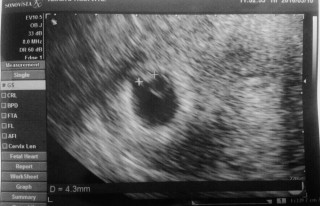

前回5w1dでは胎嚢が約1cm確認出来たものの、 それ以外は何も見えなかったのですが、 今日6w0dで行ったら胎芽、卵黄嚢も確認出来、 エコーを拡大してもらうと小さいながらも 無事、チカチカと心拍も確認出来ました! 胎嚢2cm、赤ちゃん5mm位だそうです(〃ω〃) 次回は2週間後、拡大しなくても心拍が確認出来れば 母子手帳貰いに行けるみたいなので楽しみです(*^^*)